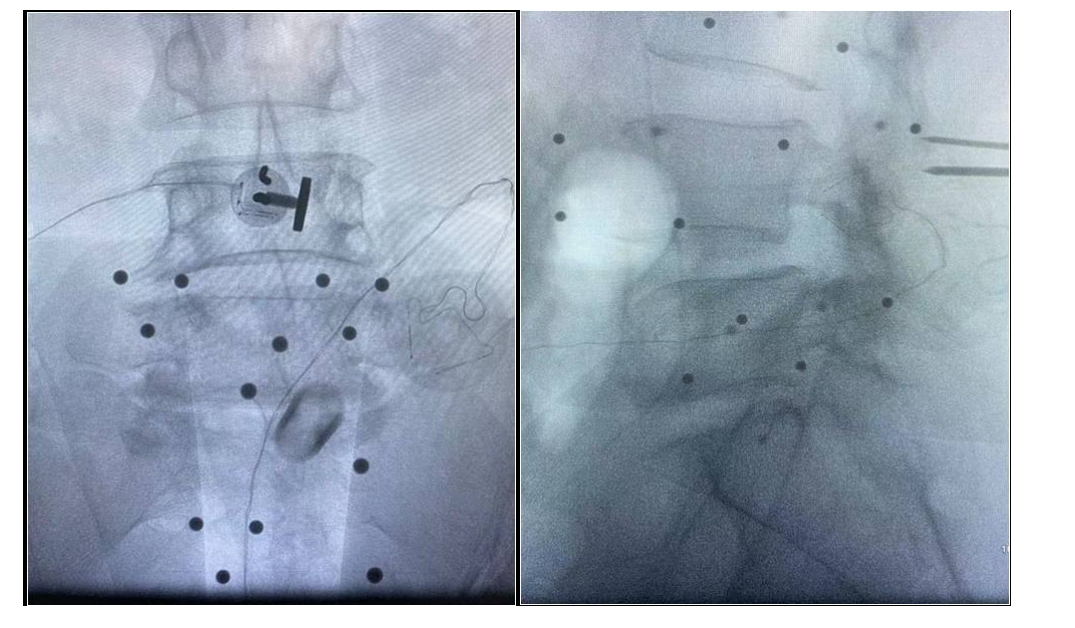

吕X,女,56岁。

主诉:腰疼及双下肢疼痛麻木伴活动受限3年加重半年。

查体:L4-5棘间及椎旁压痛,右下肢直腿抬高试验60°阳性,左下肢50°阳性,双下肢肌力肌张力正常。